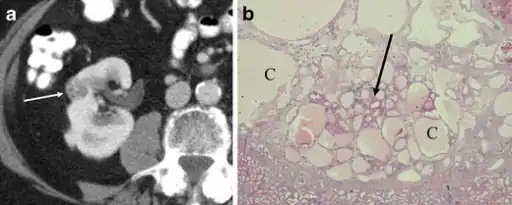

a,b)Renal oncocytoma with cystic change.

In gross appearance, the tumors are tan or mahogany brown, well circumscribed and contain a central scar. They may achieve a large size (up to 12 cm in diameter).